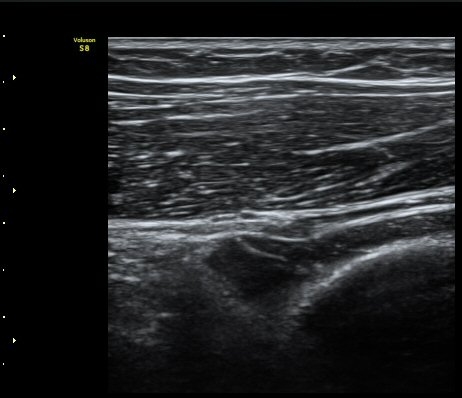

ÃÊÀ½ÆÄ °Ë»ç